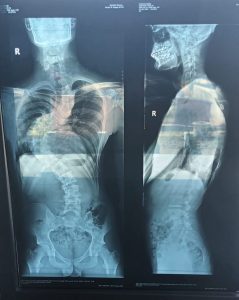

Un cavaler plin de speranțe și cu un viitor înainte suferă de Scolioză T7-T12.